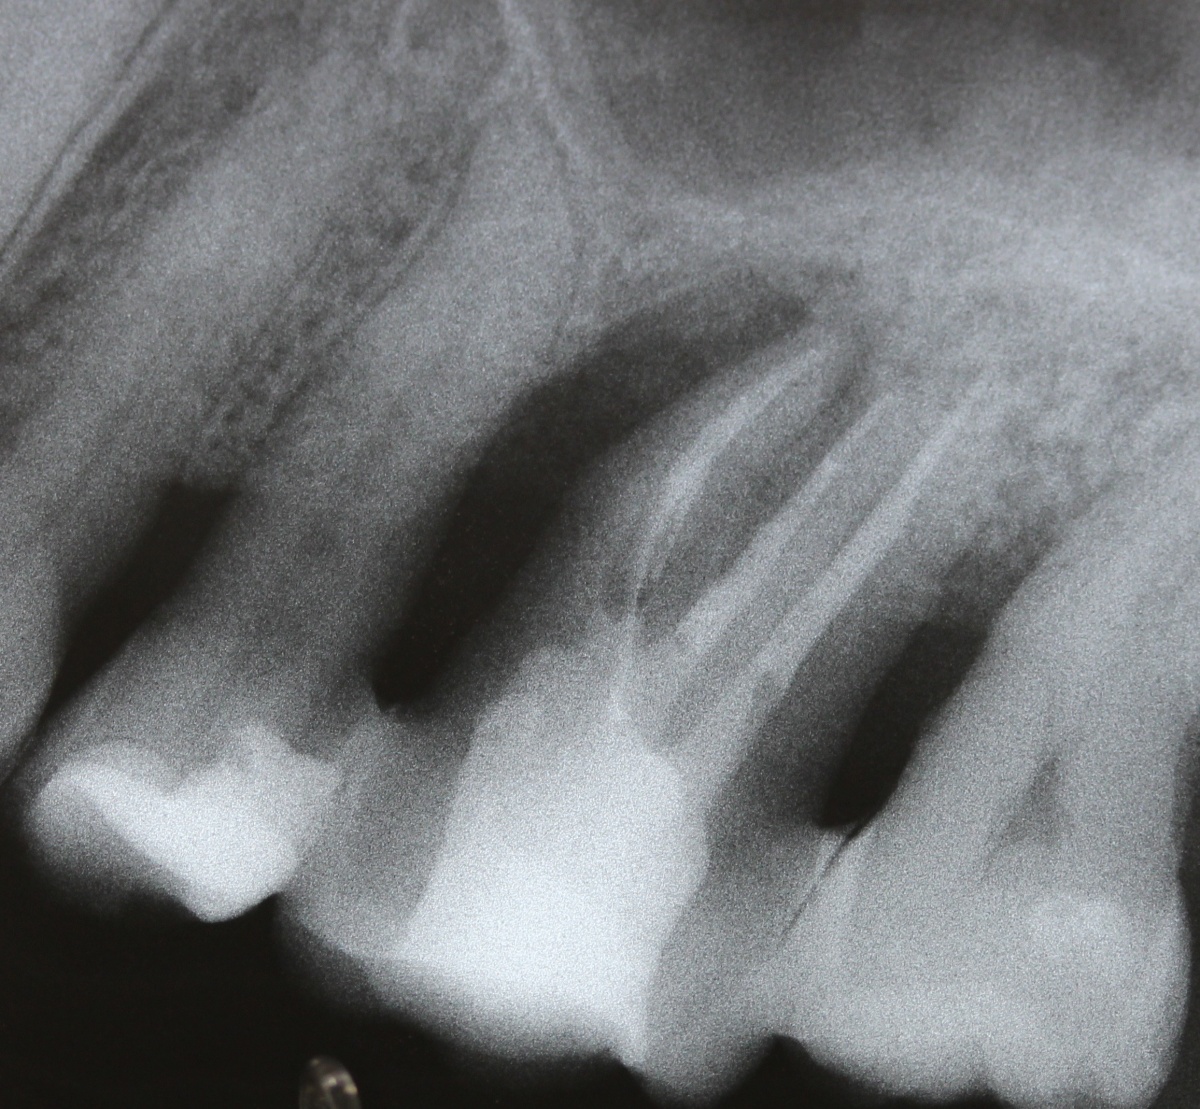

Eine Schnittstelle zu den bereits ausgeführten parodontalen Voraussetzungen des Zahnerhalts ergibt sich bei kombinierten Paro-Endo-Läsionen beziehungsweise Endo-Paro-Läsionen. Zeigen konservative Behandlungsansätze bei den meisten dieser Befunde gute Ergebnisse, ist bei einem lokal ausgeprägten Knochenabbau zumeist die chirurgische Intervention zum Zahnerhalt notwendig (Abb. 11 und 12). Wichtig dabei ist die Unterscheidung der primären Ursache (primär endodontische oder primär parodontale Ätiologie) der Läsion und einem dieser Ursache angepasstem Behandlungsprotokoll.